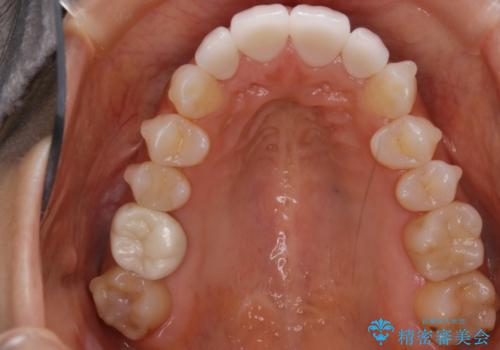

前歯・奥歯ともにセラミッククラウンで治療されている歯があったため、その歯にあまり影響が出ない範囲内で全体の噛み合わせが良くなるような動きを組み込んで治療を進めることとなりました。

被せ物がある場合

矯正治療前にセラミック等の被せ物をされている場合、それ自体の外形は矯正治療では変更することができないため、その他の天然歯の移動に影響を与えてしまう場合があります。また、治療上設定されるアタッチメント(歯の表面に付けるプラスチックの突起)が付かない場合が多く、歯のコントロールが不足する場合があります。